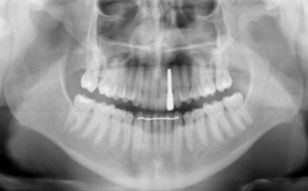

Se presenta un paciente varón de 34 años de edad, no fumador y sin antecedentes médico-quirúrgicos de interés (ASA I), que acudió a la consulta demandando una mejora en la estética de su sonrisa.

El paciente presentaba una agenesia congénita en el incisivo lateral superior izquierdo que había sido tratada previamente con ortodoncia para cerrar dicho espacio.

Tras el examen intraoral del paciente y el estudio radiográfico, se plantea la opción de tratamiento de abrir nuevamente el espacio mediante ortodoncia para rehabilitar la ausencia con un implante de circona, asegurando la estética que demandaba el paciente.